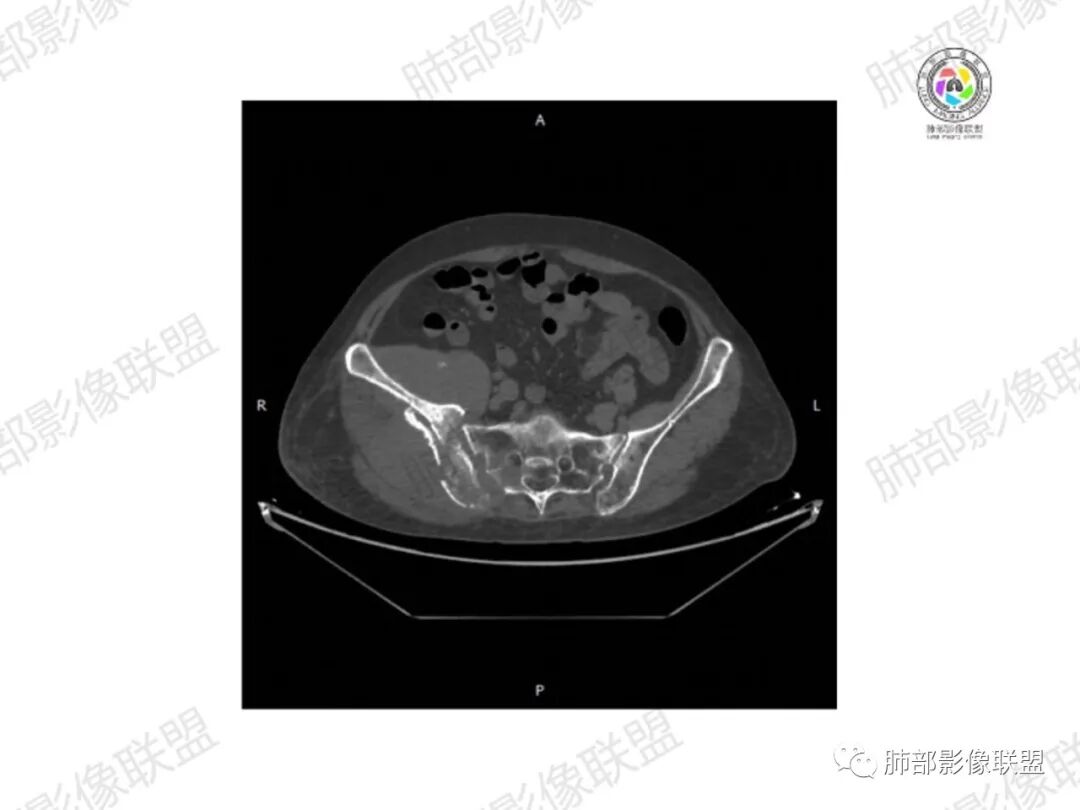

2.右髂骨轻度变形伴广泛骨质吸收破坏,边界不清且突破骨皮质。近中线区以溶骨性破坏为主,髂骨翼一侧则成骨性改变明显,骨表面见垂直骨针或花边样高密度瘤骨。

3.患骨多处皮质断裂,符合病理性骨折。注意折端可能会形成骨痂,但本例无论是形态还是部位都不符合骨痂。

4.患骨两旁(即盆骨内外)见边界不清的较大范围软组织快影,其间偶见骨化影。

1.边界不清的骨质吸收破坏,溶骨明显,骨皮质突破,软组织肿块,种种迹象表明其恶性无疑!

2.但注意这是有“成骨”的恶性骨肿瘤!我们知道老年患者的骨原发性恶性肿瘤“成骨”非常少见。少数转移瘤可为成骨型或混合型,女性患者如乳腺癌骨转移等。在男性,最典型的成骨转移是前列腺癌。

本例右侧髂骨具有较为典型的“骨肉瘤”影像学特征,有边界不清的吸收破坏、有新生骨、形成软组织肿块等等。